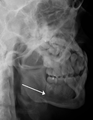

Plain film radiography

Traditionally, plain films of the mandible would be exposed but had lower sensitivity and specificity owing to overlap of structures. Views included AP (for parasymphsis), lateral oblique (body, ramus, angle, coronoid process) and Towne's (condyle) views. Condylar fractures can be especially difficult to identify, depending on the direction of condylar displacement or dislocation so multiple views of it are usually examined with two views at perpendicular angles.[10]

Panoramic radiograph of a simple mandible fracture of the right mandibular body, minimally displaced. Note that the teeth to the left of the fracture do not touch- lateral oblique image demonstrating a fractured mandible.

Towne's view of a bilateral condyle fracture. White arrow is a fracture on the neck of the condyle. Black arrow shows the condyle pulled to the medial. The same injury can be seen on the opposite side